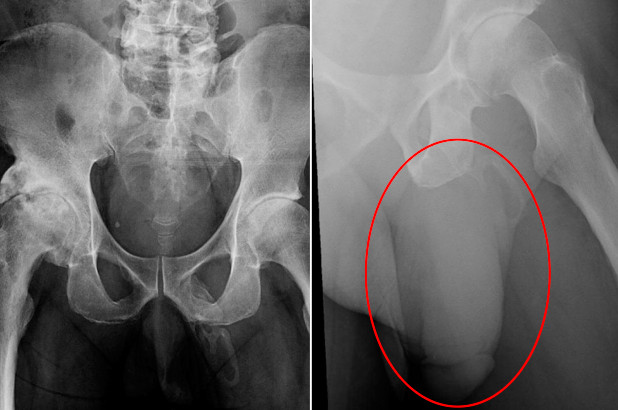

Pendant son examen, l'homme âgé de 63 ans a déclaré ressentir une douleur au niveau du pénis. Selon les médecins, sa prostate n'était pas enflée, et aucune sécrétion inhabituelle n'était à signaler. Ces derniers ont ensuite procédé à une radiographie de son bassin afin de s'assurer qu'il n'avait subi aucune fracture lors de la chute. A la place, ils ont découvert que le pénis du patient avait commencé à se transformer en os ! Les médecins ont décrit "une vaste calcification sous forme de plaque" au niveau de son organe génital.

L'ossification du pénis est une complication extrêmement rare de la maladie de Lapeyronie : en effet, seuls 40 cas ont été officiellement reportés d'après le rapport. Le problème intervient lorsque des sels de calcium (naturellement présents dans notre alimentation) s'accumulent dans les tissus mous du pénis, formant un os en dehors du squelette. D'ordinaire, cette maladie se définit comme "une déformation acquise du pénis provoquant une courbure pendant l'érection".

Ci-dessus, un schéma comparatif d'un pénis atteint de la maladie (à gauche) et d'un pénis "sain" (à droite). Tunica : corps spongieux. Corpora cavernosa : corps caverneux. Plaque : plaque fibreuse. La maladie de Lapeyronie est causée par l'accumulation de tissu cicatriciel dans le pénis, causant sa courbure.